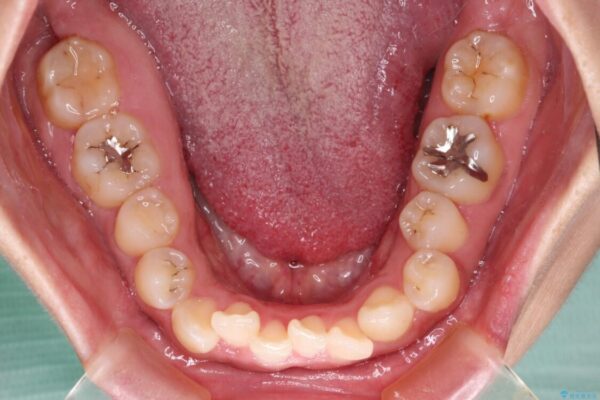

治療途中

• 【モニター】カリエール・ディスタライザーを併用した八重歯のインビザライン矯正 治療途中画像